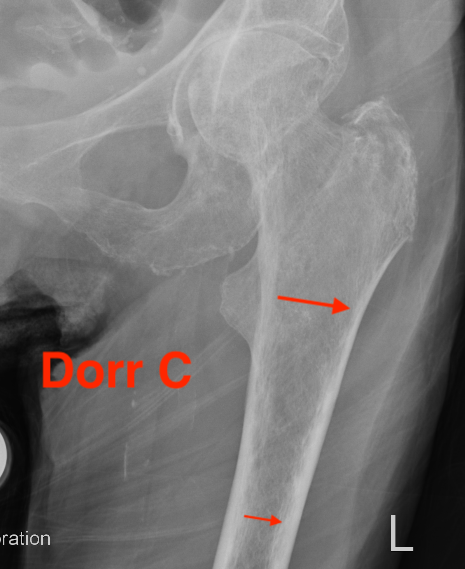

Dorr Classification of Proximal Femoral Geometry

Technique

- measure intra-medullary canal at lesser trochanter & 10cm below

- diameter 10 cm distal divided by inner diameter at midportion of lesser trochanter

- must be <75% for uncemented prosthesis

| Type A / Champagne Flute | Type B | Type C / Normal |

|---|---|---|

| Ratio < 0.5 | Ratio 0.5 - 0.75 | Ratio > 0.75 |

| Thick cortices | Wide canal diameter | |

| Young males | Elderly females | |

| Small diaphysis and thick cortex risks fracture | Cemented stem |